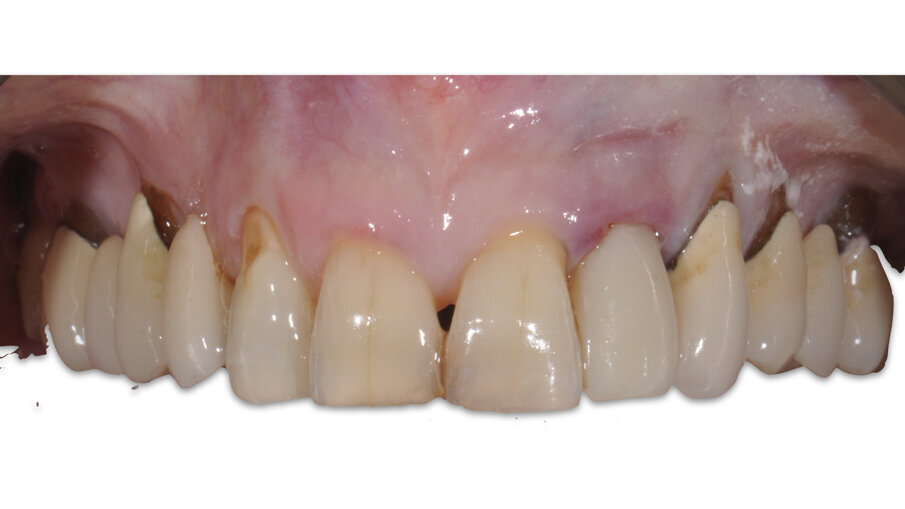

La paziente, B.G. di sesso femminile, di anni 71, è giunta alla nostra osservazione per la mobilità e lieve dolore a carico dell’elemento 2.2 (incisivo laterale superiore sinistro) (Fig. 1). All’esame ispettivo l’elemento presenta mobilità di grado 3. Al sondaggio parodontale presenta una tasca mesiale di 7 mm e di 3 mm lungo le altre superfici del dente. All’esame radiografico, eseguito con radiografia endorale periapicale, si osserva un’area di radiotrasparenza riconducibile a riassorbimento osseo soprattutto in sede mesiale (Fig. 2).

Fig. 12_Confronto tra la situazione iniziale, quella post-chirurgica e quella al termine del periodo provvisorio.